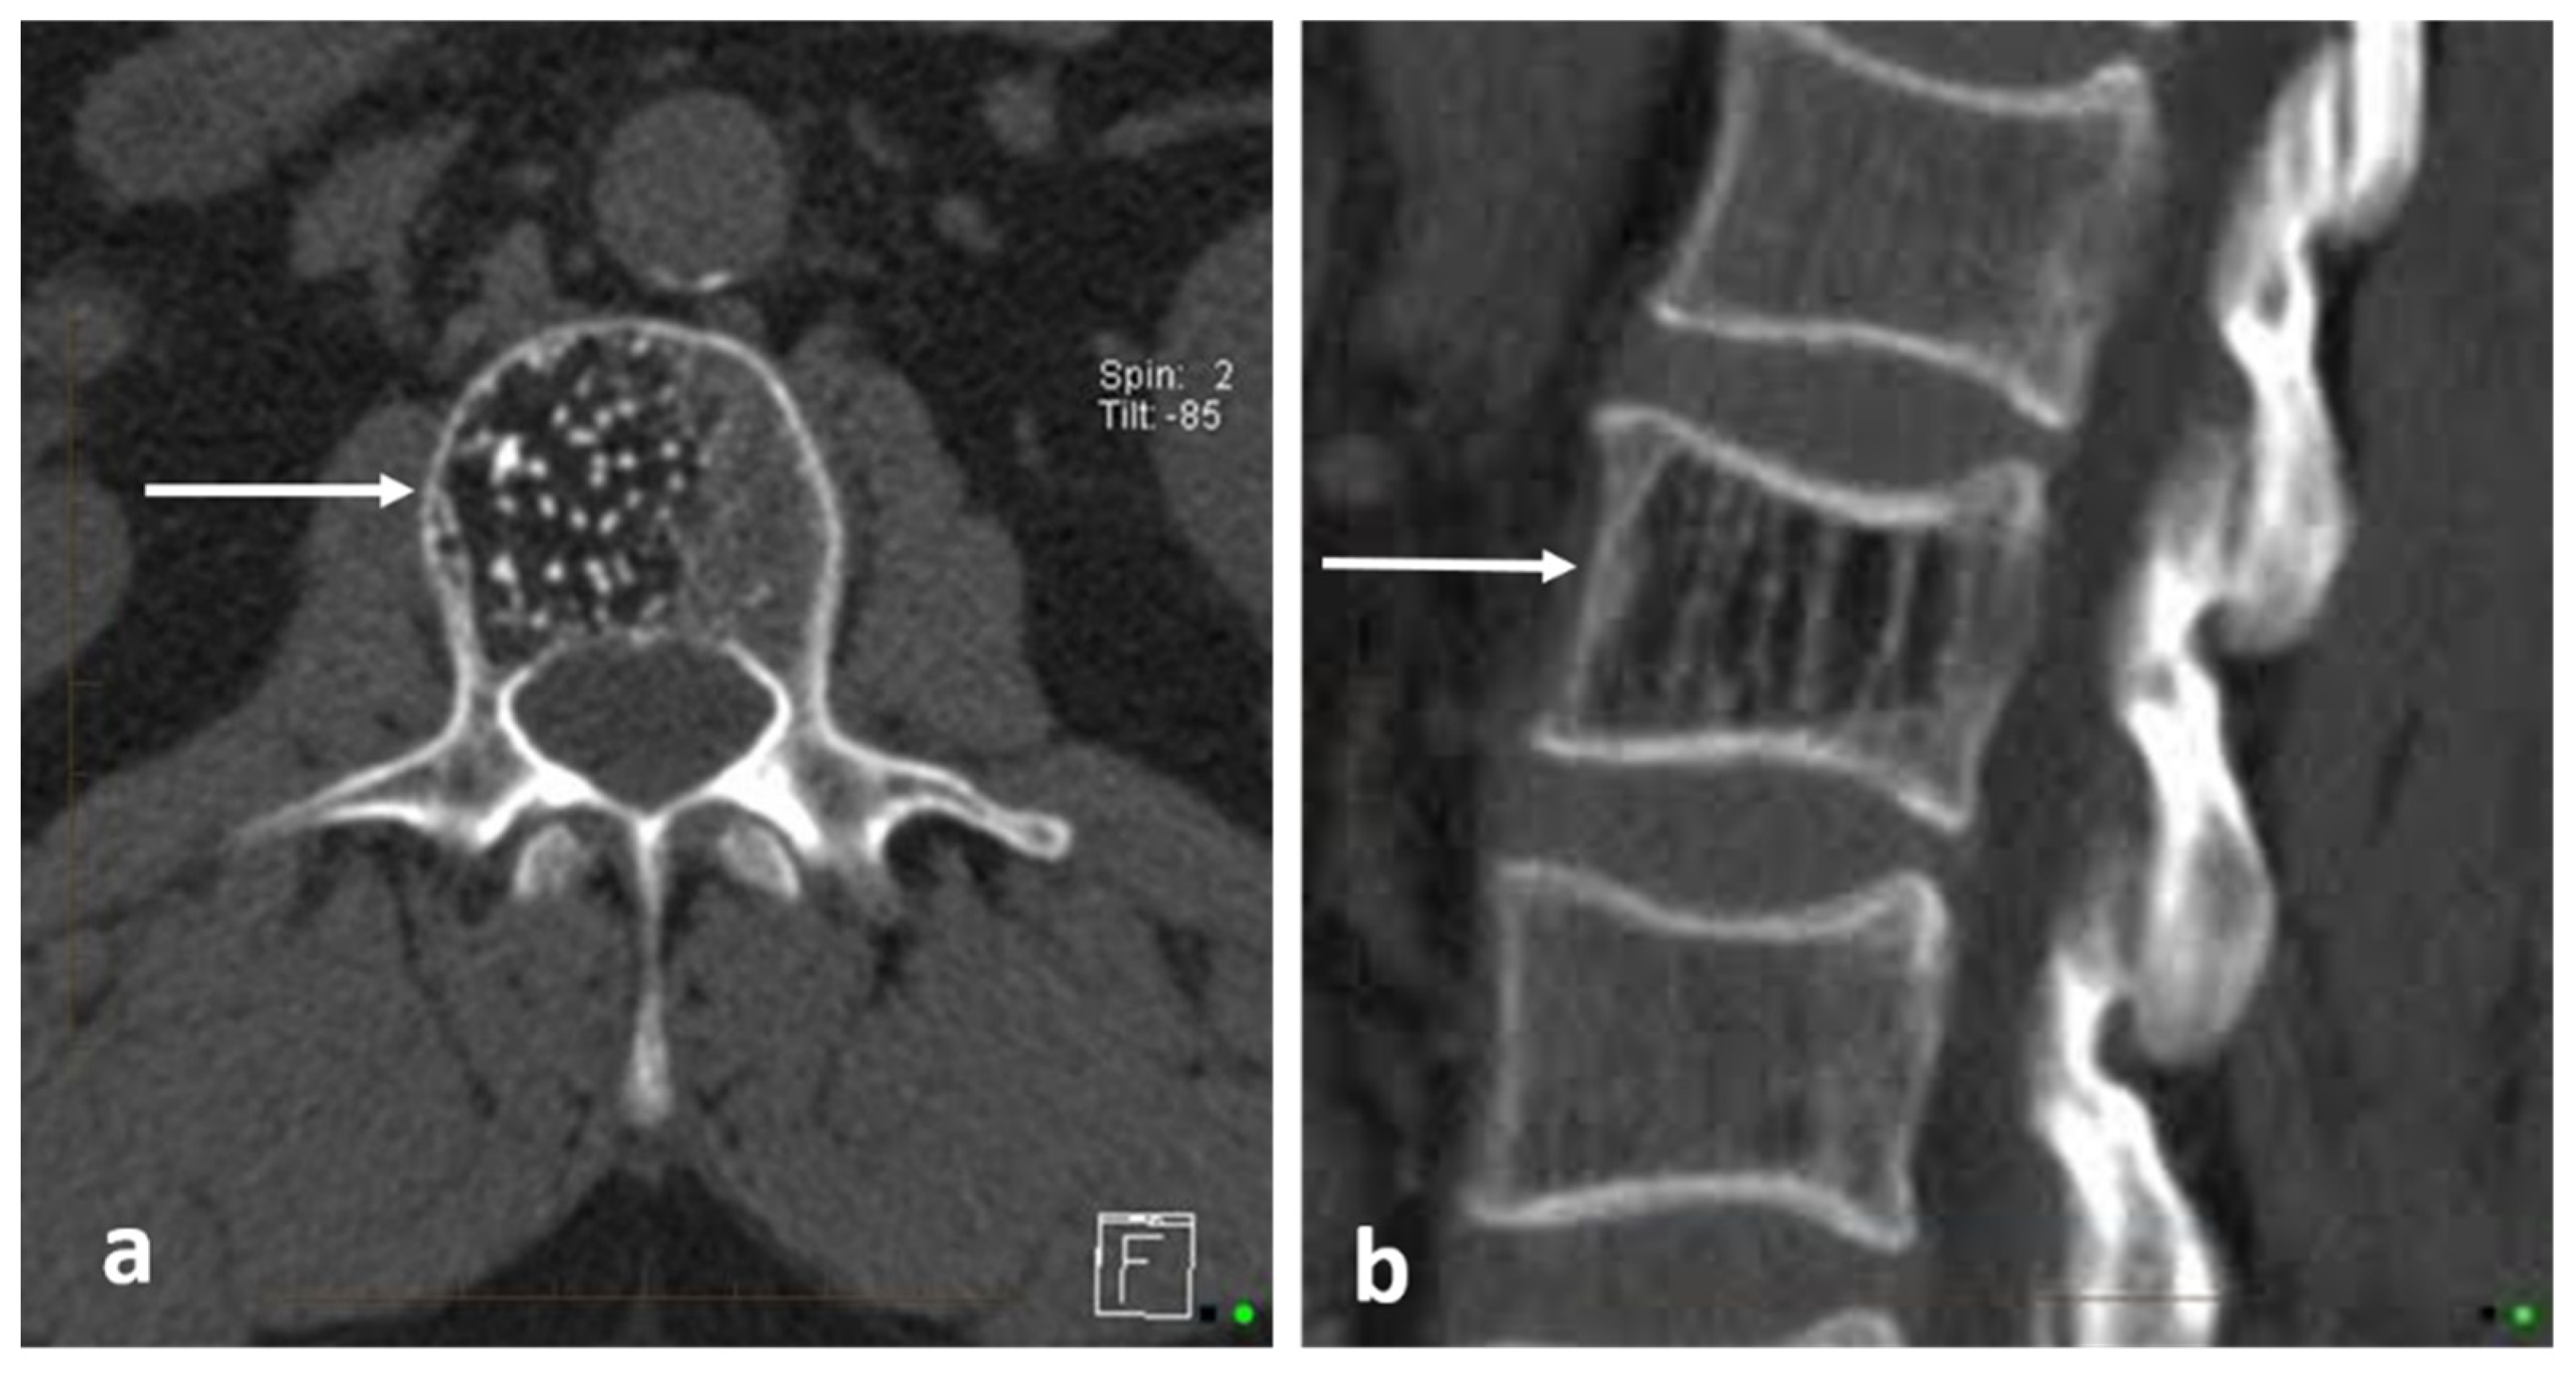

| Haemangioma | Honey comb appearance. ‘Corduroy’ and ‘polka dot’ signs. | Usually T1 and T2 hyperintense due to fat content. Signal drop out >20% on out of phase chemical shift imaging. |